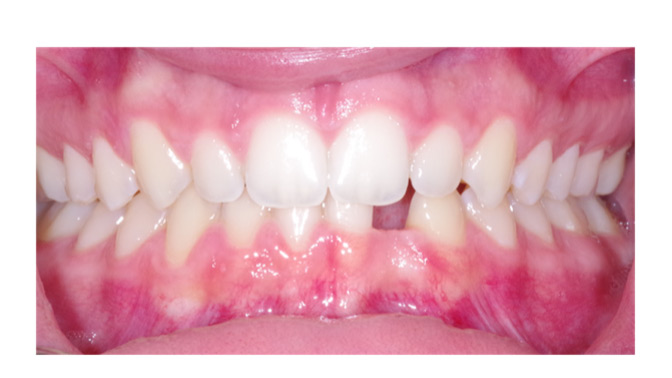

A Novel Simplified Stepwise Approach to Diagnosing Periodontal Diseases and Conditions

Prete-fig3-thumbnails alternate text for this image

Abstract Background: The classification system for periodontal diseases and conditions was revised in 2017. Evidence-based criteria were developed, and extensive revisions made, to reflect advancements regarding the etiology and progression of periodontal diseases. Among the many updates made to the previous classification system, a novel definition for periodontal health was introduced, along with a staging … Read more